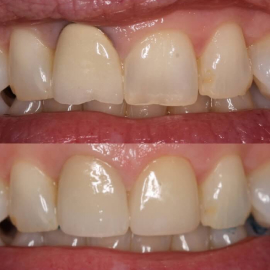

Ceramics can make a smile look nice again

Opening the bite position provides a more stable

position also protecting the front teeth